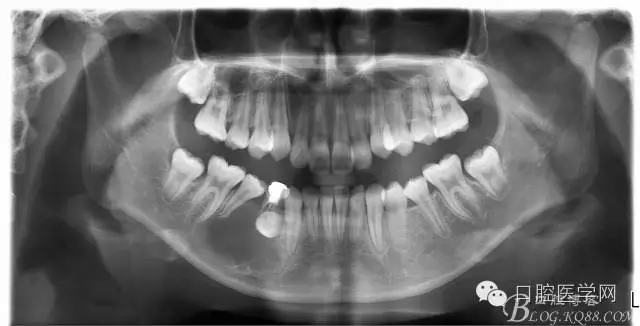

查:右側(cè)第二前磨牙第一乳磨牙恒尖牙頰側(cè)前庭溝隆起,捫有乒乓球感。曲斷及CT示:右側(cè)第二前磨牙第一乳磨牙恒尖牙根尖區(qū)有一囊腫,頰舌側(cè)骨板極薄,牙根無吸收,第二前磨牙牙根位于囊腫中,第一雙尖牙牙冠遠(yuǎn)中水平向阻生,牙冠位于囊腫中。經(jīng)協(xié)議:手術(shù)摘除創(chuàng)傷大,同意開創(chuàng)引流保守治療。

術(shù)后一個月 三個月 五個月 八個月 拔除第一雙尖牙后 曲斷片: